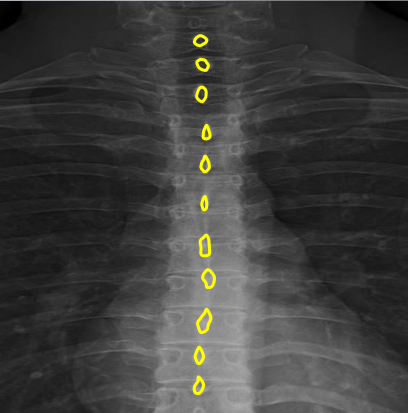

Vertebral bodies

Superior and inferior endplates

Disc space

Disc spaces

End plate tips

Femur heads

Superior iliac crests

Lateral iliac crests

Ischial tuberosities

Obturator foramen

S2 tubercle

Pubic symphysis

Sacral groove

Lateral aspect of sacrum

Medial aspect of ilium